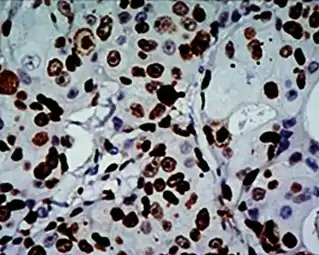

High Ki-67 expression in an invasive breast cancer, with cancer nuclei being stained (brown). There is tumor cell positivity in 70% of the cells:

High Ki-67 expression in an invasive breast cancer, with cancer nuclei being stained (brown). There is tumor cell positivity in 70% of the cells:

Ki-67 labelling index = 70% Counting positive versus negative nuclei with Ki-67 labeling, in this case in a neuroendocrine tumor of the small intestine. To count as positive, a nucleus should be at least half within the field of view, be large enough, and not be located in the stroma. Otherwise, even weakly positive nuclei count as positive.